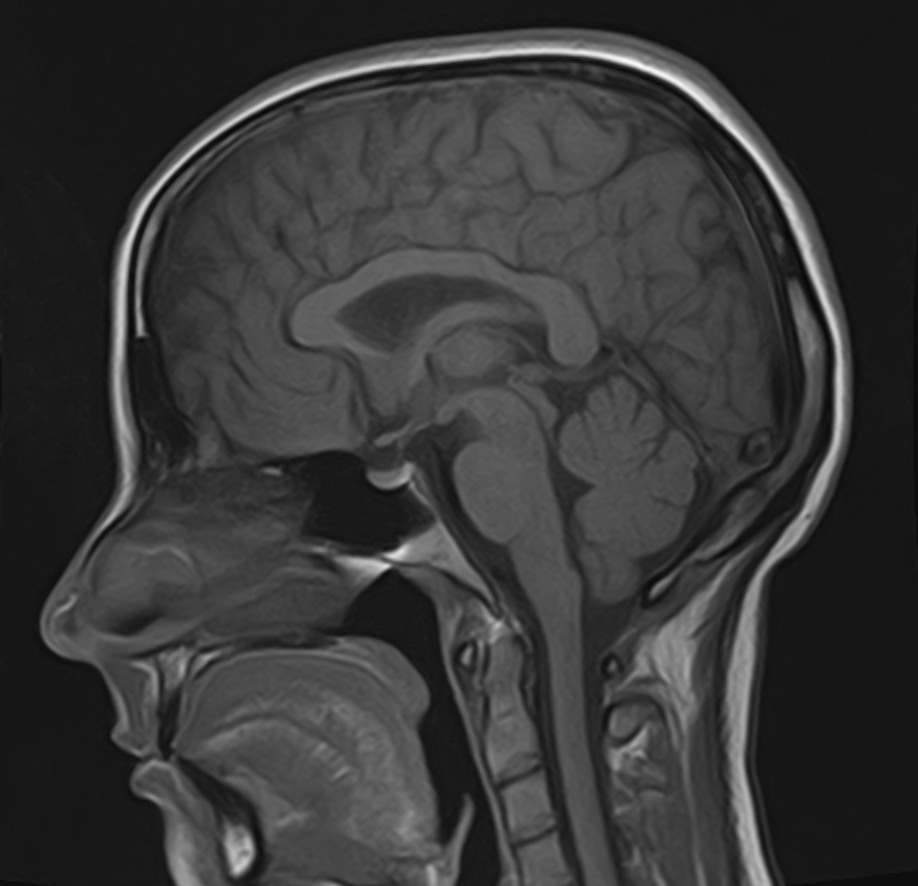

МРТ головного мозга является наиболее информативным, безопасным и доступным методом исследования, который позволяет оценить состояние всех структур и сосудистой системы головного мозга, выявить возможные патологические процессы.

Что показывает МРТ головного мозга

С помощью  магнитно-резонансной томографии можно диагностировать следующие патологии:

• опухолевые образования доброкачественного и злокачественного генеза;

• кистозные образования и псевдокисты;

• очаги ишемического инсульта, кровоизлияния на фоне геморрагического инсульта;

• воспалительные процессы со стороны мозговых оболочек и тканей головного мозга (менингиты, энцефалиты);

• демиелинизирующие заболевания головного мозга, в том числе рассеянный склероз;

• дегенеративные изменения в структурах головного мозга (болезнь Паркинсона, болезнь Альцгеймера, старческая деменция);

• травматические повреждения головного мозга, наличие гематом;

• изменения структуры ткани головного мозга, характерные для эпилепсии;

• патология со стороны сосудов головного мозга (аневризмы, сужение просвета сосудов, сосудистые мальформации).

Стандартная МРТ головного мозга проводится без использования контрастных веществ. В ряде случаев исследование проводится с внутривенным введением контраста, содержащего соли гадолиния (Омнискан, Магневист и др). Контрастное вещество попадает в кровоток и при сканировании МР-томографом измененные участки становятся лучше видимыми, что помогает в диагностике таких заболеваний, как рассеянный склероз, способствует выявлению опухолевых новообразований и некоторых сосудистых патологий.